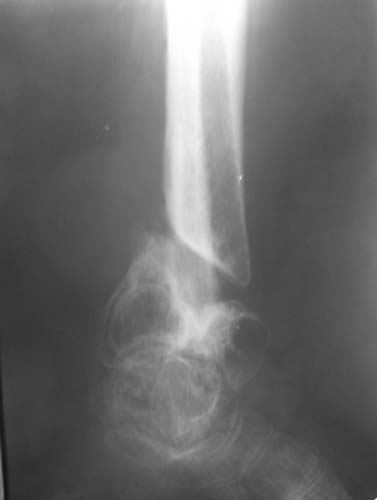

Женщина, 62 года. Травма 2 года назад в результате ДТП. Находится на лечении с 30.10.06 года с диагнозом: Несросшийся перелом дистальной трети правой большеберцовой кости с угловыми деформациями дистального отдела конечности, дефектом костной ткани.

Рубцовой деформацией мягких тканей медиальной поверхности дистальной трети голени. Нейротрофические нарушения. Посттравматический остеопороз. Дегенеративно-дистрофический остеоартроз правого голеностопного сустава.Сопутствующая патология.: ЖКБ, хронический калькулезный холецистит в стадии ремиссии. МКБ, хронический пиелонефрит в стадии ремиссии.Ожирение 3 ст. Посттромбофлебитический синдром нижних конечностей, ХВН 2 ст. Посттравматическая нейропатия левого малоберцового нерва с парезом левой стопы. Какие предложения по тактике лечения? Заранее благодарю!

> лечении с 30.10.06 года с диагнозом: Несросшийся перелом дистальной

> трети правой большеберцовой кости с угловыми деформациями дистального

Голеностопный сустав тут, видимо, потерян. Так что надо думать только про стабилизацию. Какие из существующих вариантов артродеза доступны, и какой из доступных оптимален? Антон, есть ли смысл обсуждать варианты с закрытым штифтованием, доступно оно? Если да, то Алексей Семенистый предлагает вполне жизнеспособный план (хотя можно и антгерадно сделать). Если нет, то надо что-то придумывать с аппаратом. Наверно, латеральным доступом кпереди от fibula с ее пересечением открыться, и что-то костно-пластическое делать.